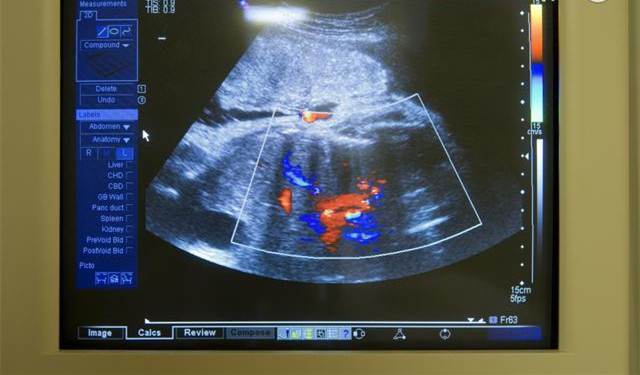

一般来说,胎儿的胎心最早在孕10周就可以通过仪器测出来,目前,比较普遍运用到的多普勒的高灵敏度仪器,可以在胎儿10周或者12周的时候,,便可以听到像马蹄声一样的心跳。不过,也有些医院可能采用一般的听诊器,这样的话,就要到17-18周才能追踪到胎儿的心跳声。还有一种情况是,妊娠初期,由于胎儿的位置关系,或者其他种种干扰因素,比如母体的脂肪过厚等原因,即使用极精密的仪器也无法听到胎心音。胎心一般在孕7周左右会出现,孕早期发现没有胎心,可以多换几家医院检查,如果还是没有胎心,即可能是胚胎停育。